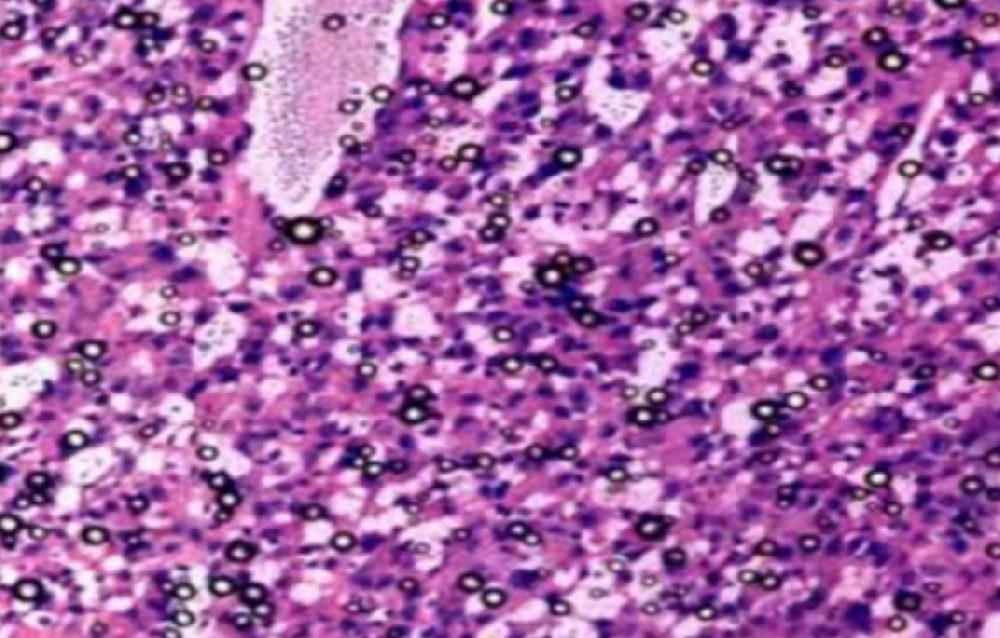

实验外包——了解一下病理组织冰冻切片

冰冻切片(frozen section)是一种在低温条件下使组织快速冷却到一定硬度,然后进行切片的方法。因其制作过程较石蜡切片快捷、简便,而多应用于手术中的快速病理诊断。冰冻···